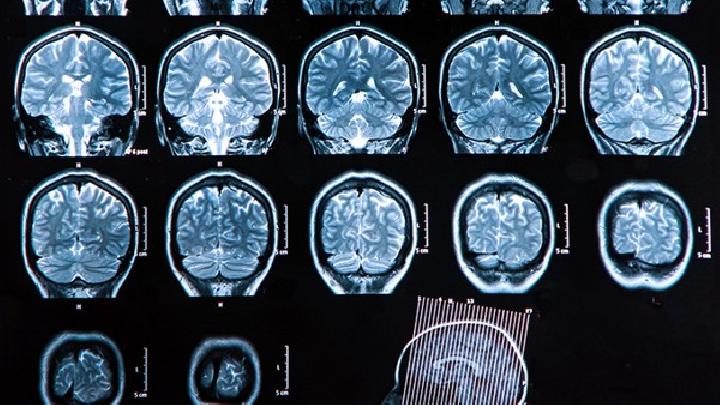

脑瘫儿童可通过康复训练、药物治疗、手术治疗、辅助器具等方式治疗。脑瘫通常由产前脑发育异常、围产期缺氧缺血、产后脑...

脑瘫可能由产前缺氧、早产低体重、新生儿黄疸、遗传代谢异常等原因引起,症状表现为运动障碍、肌张力异常等,需通过康复...

脑瘫病无法完全治愈,但可通过康复训练、药物治疗、手术治疗、辅助器具等方式改善功能。脑瘫是由非进行性脑损伤导致的运...